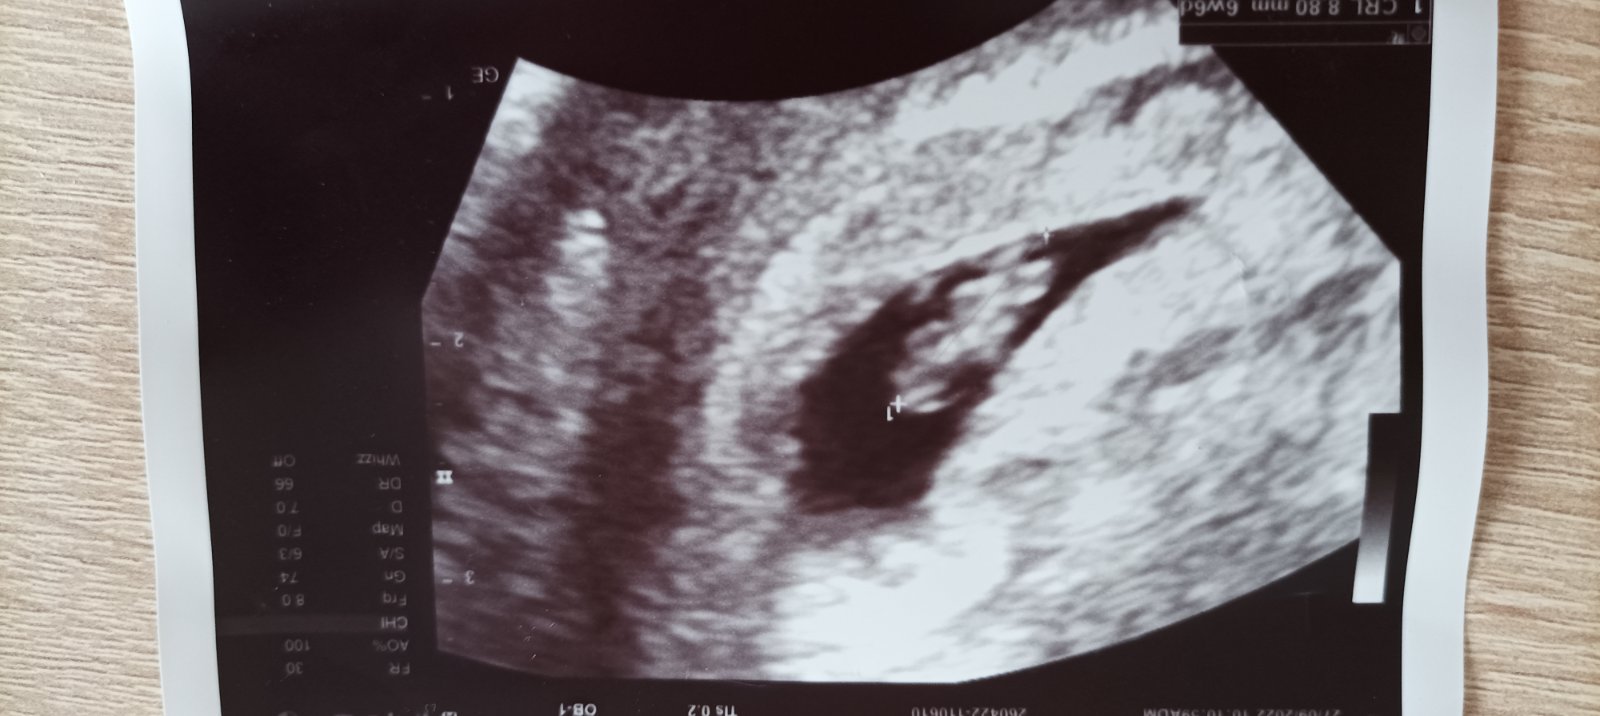

Tak je to potvrzeno 🙂 Dnes dle výpočtů 5+2 a HCG z pátku kdy na UTZ skoro nebylo nic vidět 1794. Další kontrola 21.10.

@kackabis Mě právě paní doktorka říkala ať přijdu hned, takže jsem volala jak se mi to potvrdilo na testu s tím, ať rozhodne ona kdy mám přijít a říkala, že mě chce vidět hned. Takže jsem šla za dva dni po té. Tedy nějaký 4tt+2 a na utz byla jen skvrnka, tak mi vzala krev a HCG 1794. Další kontrola 21.10. a to už doufám bude vidět srdíčko ❤

U mě vždy srdicko 6+